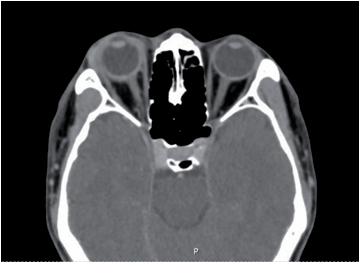

Herpetic Acute Retinal Necrosis (ARN) Complicated by Panophthalmitis - A Rare Ocular Presentation: A Case Report

Papavarin Sirikietsoong, Supinda Leeamornsiri, Kittichai Akrapipatkul, Naruechanok Lertkusol, Suntaree Thitiwichienlert, Kosol Kampitak, Paiboon Bowornwattanadilok

42-46